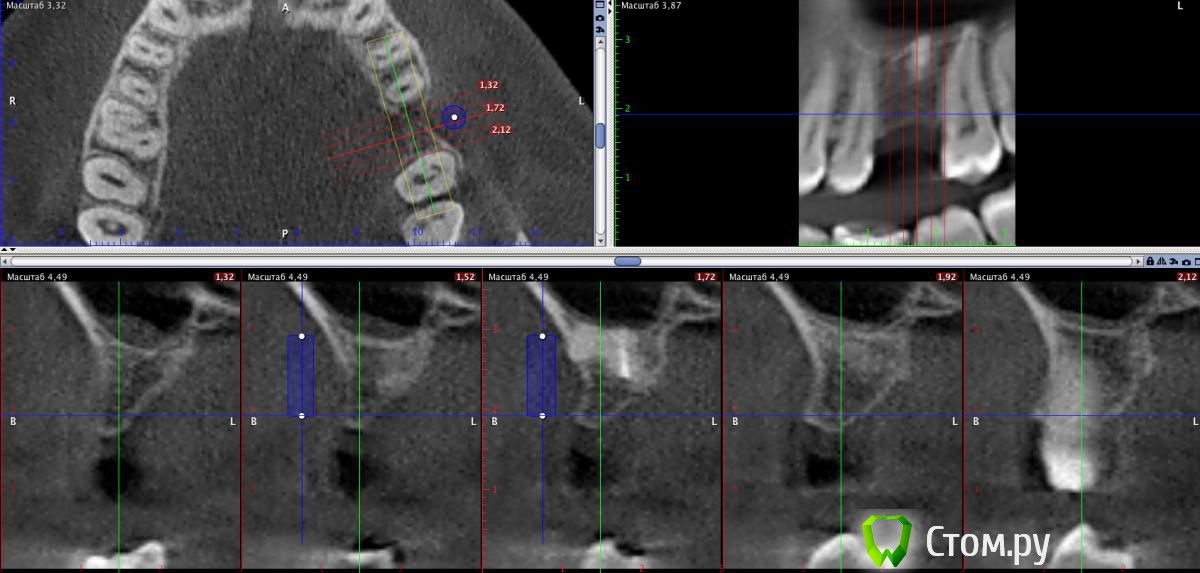

stommm Опубликовано 24 июня, 2014 Поделиться Опубликовано 24 июня, 2014 (изменено) Уважаемые коллеги, обратился пациент с желанием восстановить утраченные 41 и 26. На кт картина следующая: 41: по аксиальному срезу хочется добавить блок (ламинат) вестибулярно, но по боковым срезам кажется еще и язычно надо добавить26: удалить апексы, потом либо небно нарастить ширину тем же ламинатом, либо сделать синус и поставить имплант апикальнее. На картинке для сравнения нарисован имплант 4*10. Как бы вы поступили в такой ситуации? Может лучше заменить ламинаты ламинами и сделать мпк? Изменено 24 июня, 2014 пользователем stommm Ссылка на комментарий